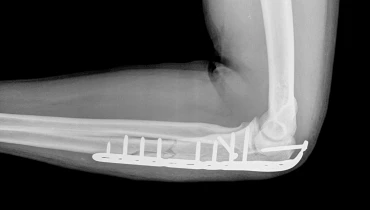

Остеосинтез предплечья – это хирургический способ вернуть костям предплечья (лучевой и локтевой) ось, длину и стабильность после травмы. Суть процедуры: выполняется точная репозиция отломков, затем надежная фиксация специальной конструкцией – пластиной, винтами, спицами, интрамедуллярным имплантом или внешним аппаратом. Благодаря этому восстанавливается анатомия, суставы работают согласованно, а вращательные движения кисти («пронация-супинация») возвращаются без болей и хруста. Метод позволяет рано начать разработку, сделать лечение предсказуемым и сократить сроки бытового и спортивного возвращения к обычной нагрузке.

• Накостный. Пластина ложится на кость и удерживает фрагменты с угловой стабильностью; дает точную репозицию и компрессию. Остеосинтез предплечья пластиной – золотой стандарт при диафизарных и метафизарных линиях, особенно если требуется восстановить радиус-дугу для правильной кинематики лучевого сустава.

Принцип остеосинтеза предплечья: аккуратный доступ, бережное обращение с мягкими тканями, точная репозиция, стабильная фиксация и проверка в двух-трех плоскостях. Длительность зависит от уровня, числа фрагментов и состояния кожи, но цель всегда одна – анатомия, стабильность, ранние движения.

Фиксация

Пластины с угловой стабильностью, компрессионные винты, интрамедуллярный штифт или внешний аппарат – то, что лучше удержит ось и длину.